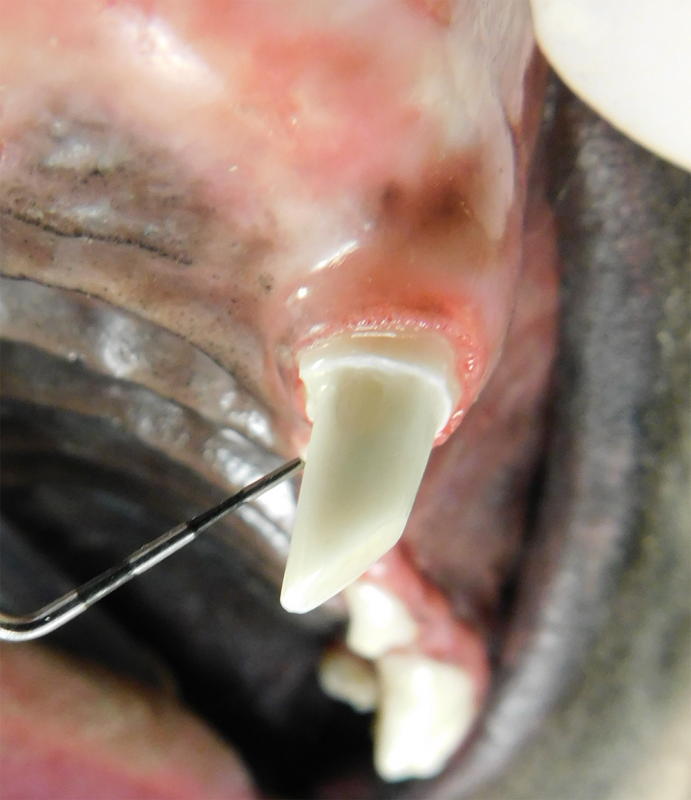

Tooth Resorption

Tooth resorption is a disease process where the body begins to break down the adult tooth. It is widely known to occur in cats but can also occur in dogs. In cats these lesions are thought to be inflammatory, while in dogs they can be more of a replacement resorption process. These lesions can be very painful and should be treated, generally with extraction depending on the type of resorption that is occurring. The disease can be progressive and affect many teeth over several years. It is important to have regular checkups and yearly dental cleanings to monitor for these lesions.